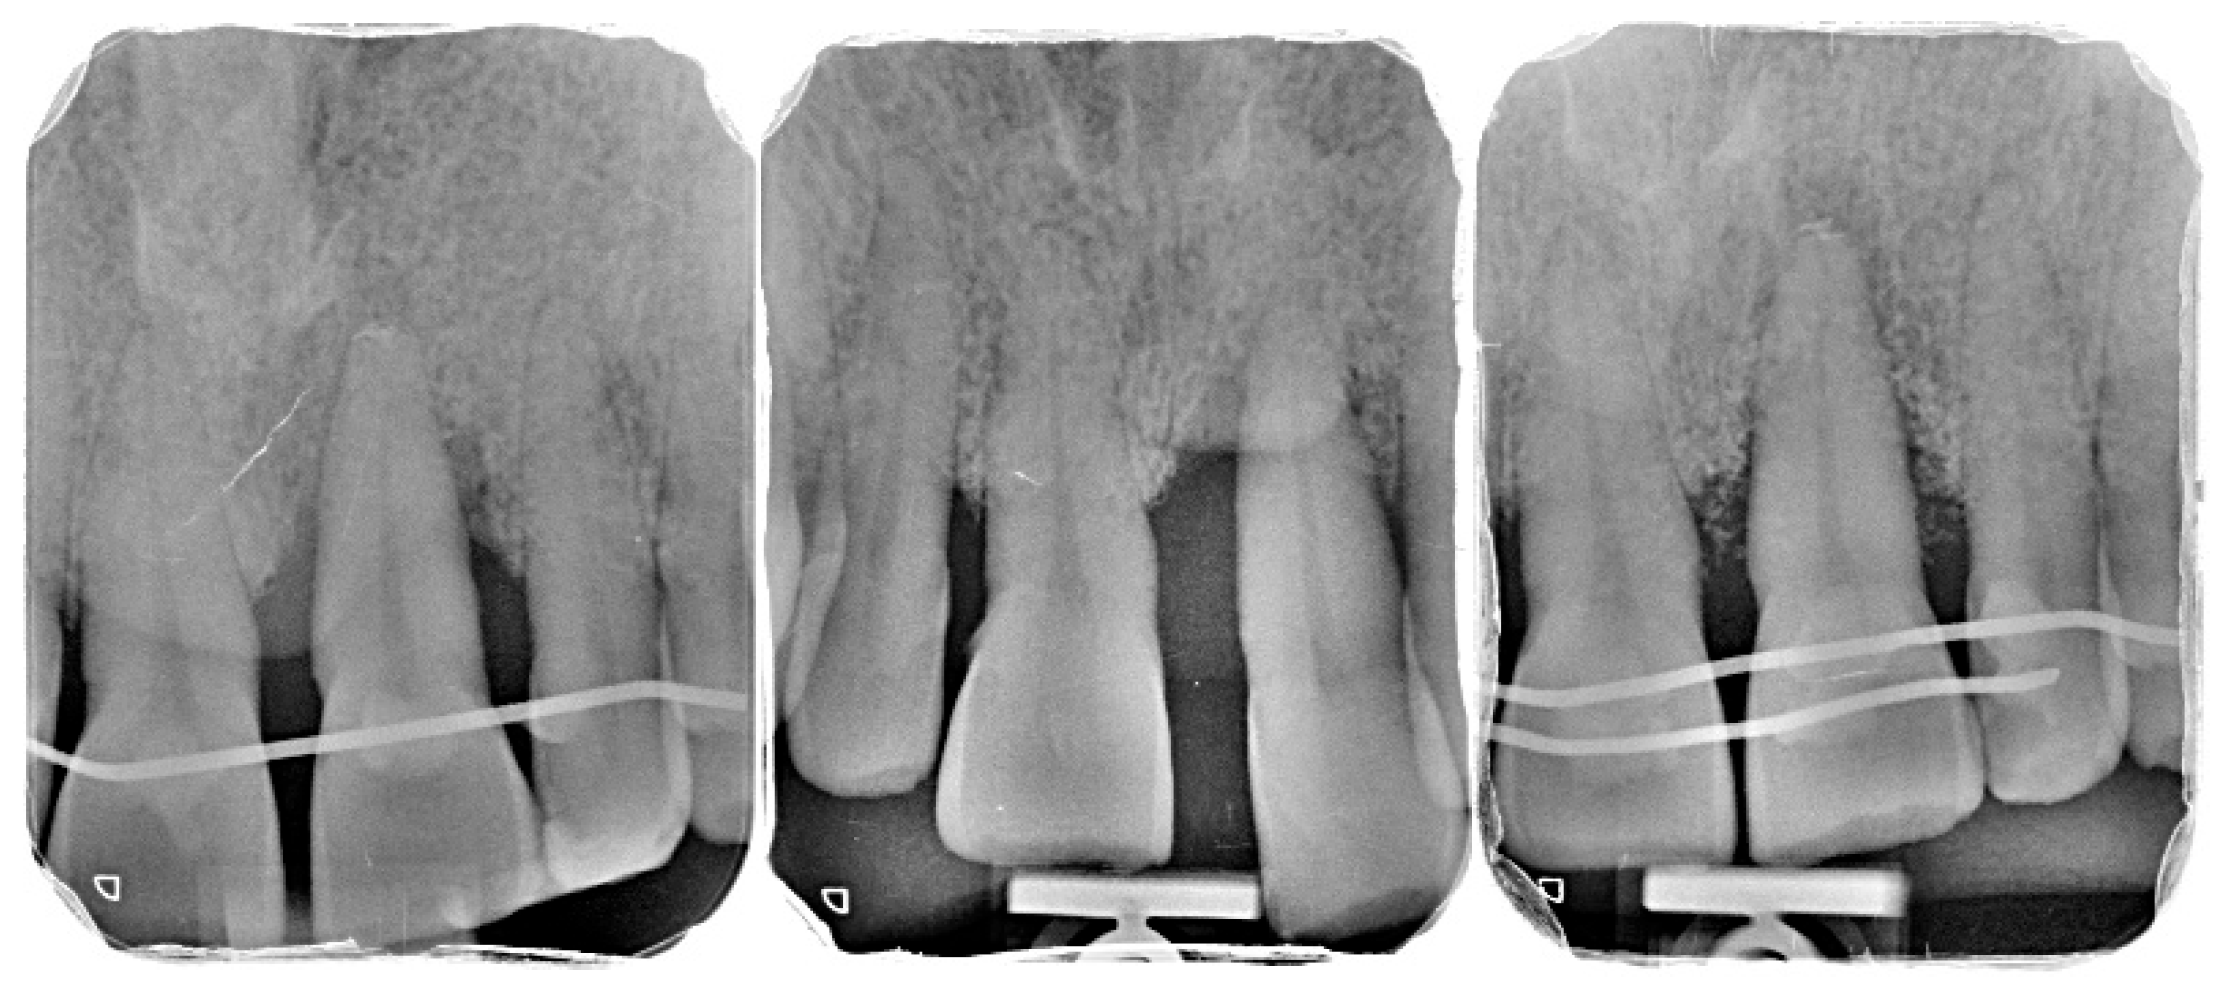

2.2. Patient Information and Periodontal Diagnosis

2.3. Initial Periodontal Therapy

3.2. Radiographic Findings